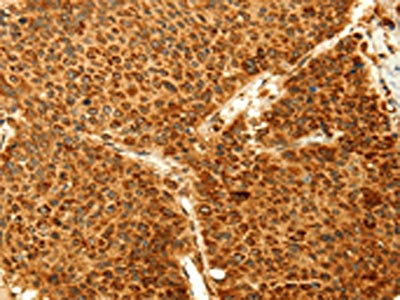

The image on the left is immunohistochemistry of paraffin-embedded Human liver cancer tissue using CSB-PA449040(GRM3 Antibody) at dilution 1/50, on the right is treated with fusion protein. (Original magnification: ×200)